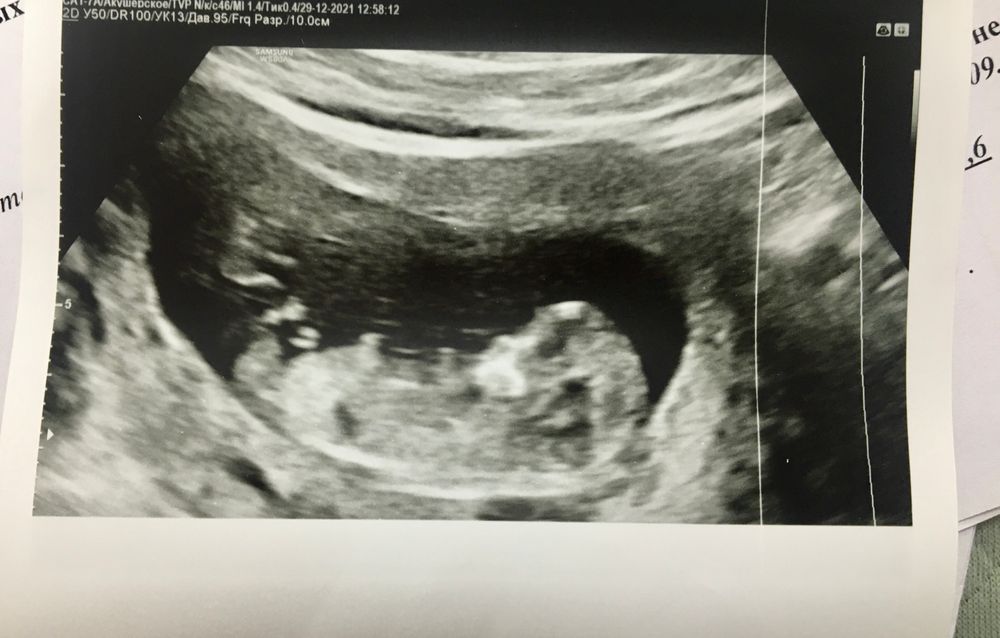

Угадайка по снимку...пол:)

Пол малыша

Чисто интересно послушать ваши предположения)) может по телосложению вам кто-то видится? Чсс 163 в 12-13 недель (знаю что особо это за показатель Пола не считают) Эксперт на самом узи ничего не предположила, сказала рано ещё) это 1 скрининг

А это разве не бугорок? Если это он, то девчуля у вас😍

Мария //рожу дочку в 2021//, ого, даже не обратила внимания) он как бы за ногой, но узи видит?

Elle Light, просто полового бугорка торчащего не вижу))А по очертаниям предположила бы мальчика)